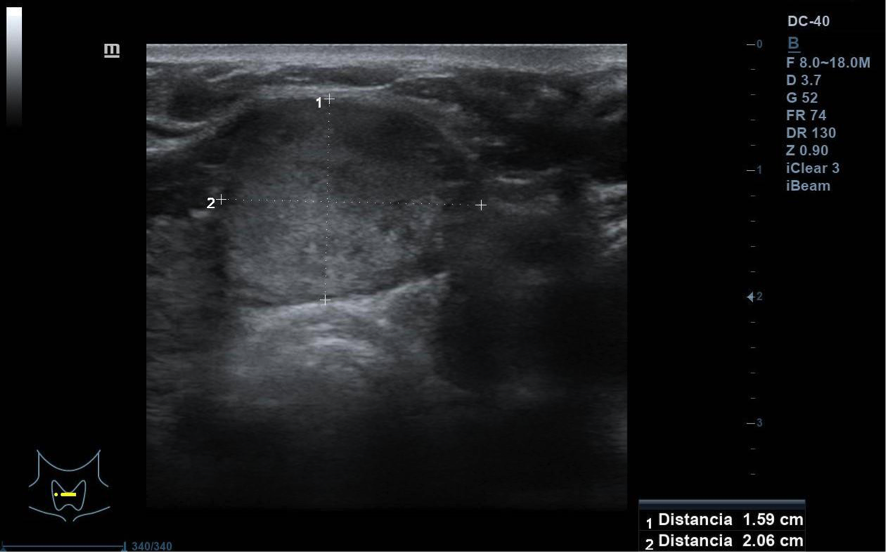

Se visualiza nódulo tiroideo en la unión del istmo con lóbulo tiroideo derecho, sólido, con cierta heterogenicidad, halo grueso anecogénico. Una zona del borde irregular, con mayor señal Doppler y de crecimiento excéntrico. Mide de diámetro máximo 25 x 20 mm. Adenopatías no patológicas.